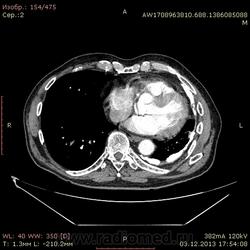

Доброго времени суток уважаемые форумчани! :)Провели исследование КТ грудной клетки с контрастированием, для выявления аневризмы грудного отдела аорты. В результате увидели это:

??? Аневризму честно не вижу (мало опыта в определении аневризм). Тромбоз в бассейне верхней полой вены. В левом легком обызвествленные плевральные шварты? как исход осумкованного плеврита неизвестной давности?

Ребята, вы что, какая жидкость? Чистая известь, посмотрите в костном окне. Отставить натив (в данном случае, хотя для аневризм он обычно нужен). Отставить тромбоз верхней полой вены (потоковые артефакты, не дело вены в артериальную фазу оценивать). Отставить аневризму  аорты, поперчник восходящего отдела на уровне легочного ствола 42мм. А вот легочная гипертензия, здравствуй: поперечник легочного ствола - 37мм, ПЛА - 25мм, ЛЛА - 25мм, НАо - 25-34мм.